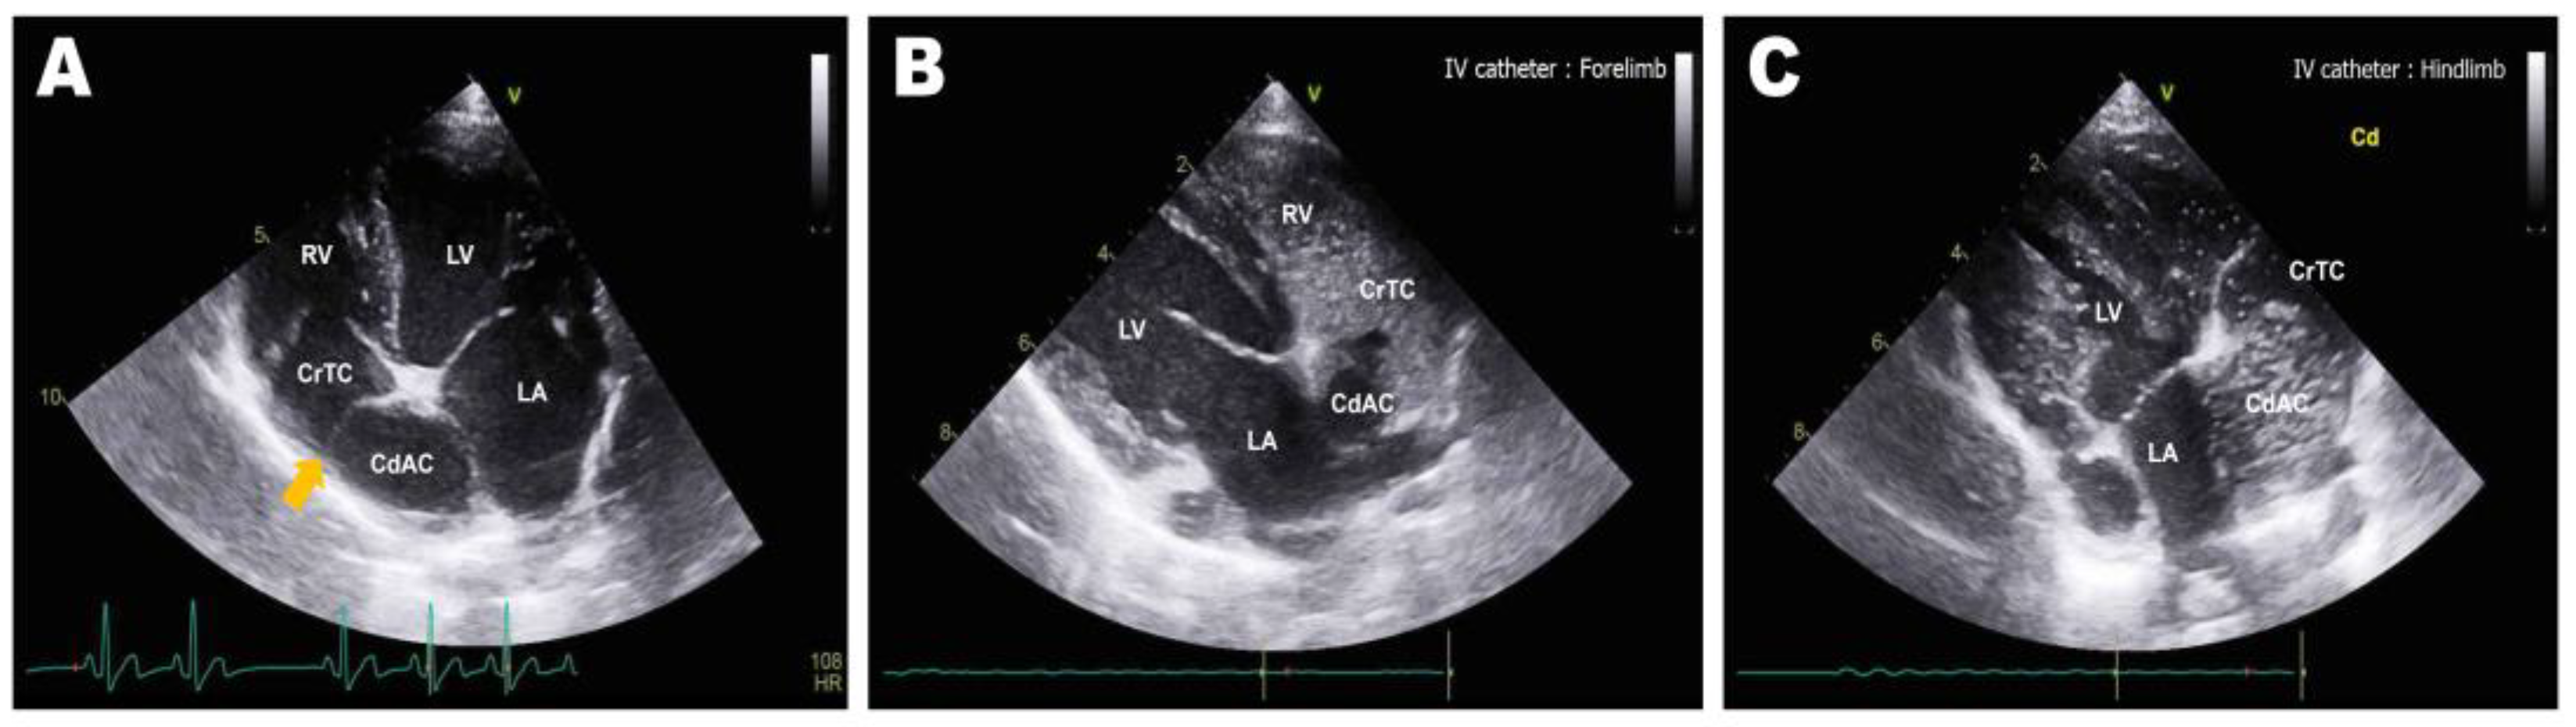

Abdominal radiographs showed severe abdominal distention and a loss of serosal detail (Figure 1); no significant findings were observed apart from these. Transthoracic echocardiography showed an echo-dense, band-like structure within the right atrial chamber, extending from the atrioventricular junction to the free atrial wall (Figure 2A). The right atrium was divided into cranial and caudal chambers. Color Doppler imaging revealed continuous venous blood inflow from the caudal chamber to the cranial chamber through a perforation in the remnant membrane, confirming an abnormal venous blood inflow in the right atrium. An agitated saline study was performed using 3 mL of normal saline to further characterize the flow in the right atrium. Microbubbles were made with saline solution, two syringes, and a three-way stopcock. These were injected in the left cephalic vein and the contrast was noted only in the right atrial cranial chamber and the right ventricle immediately afterward (Figure 2B). When the microbubbles were injected in the left lateral saphenous vein, these reached immediately the right atrial caudal chamber; and some moved into the cranial chamber through a perforated membrane (Figure 2C). This confirmed the presence of a cranial true chamber (CrTC) and cranial vena cava (CrVC) as well as a caudal accessory chamber (CdAC) and caudal vena cava (CdVC). A thoracic computed tomography scan was performed using 30 mL of iohexol contrast agent (Omnipaque, GE Healthcare China). Strong contrast enhancement was observed in the cranial chamber that communicated with the CrVC (Figure 3) during the dextrophase (25 s after contrast injection); in contrast, weak contrast enhancement was observed in the caudal chamber connected to the CdVC. A venous blood inflow obstruction was observed in the right atrium connected to the CdVC, suspected of causing severe ascites. Based on these imaging findings, the patient was diagnosed with CTD, and surgical correction was advised. Both interventional procedures and open-heart surgery can be options for treating CTD. However, considering the potential risk of re-stenosis following interventional treatment, a curative resection involving surgical membranectomy via VIO was planned.

Figure 1. Preoperative abdominal radiography: ventrodorsal (A) and lateral (B) views. Severe abdominal distention and decreased serosal detail were observed due to ascites.